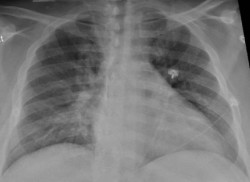

La tomosíntesis con mamografía sintética mejora la detección del cáncer de mama

La tomosíntesis digital de mama (TDM) en combinación con la mamografía sintética mejora la detección del cáncer sobre la mamografía digital sola, según un estudio de investigadores italianos publicado en la revista `Radiology`. Los resultados del estudio añaden más apoyo al uso de TDM en programas de detección de cáncer de mama basados en el cribado poblacional.